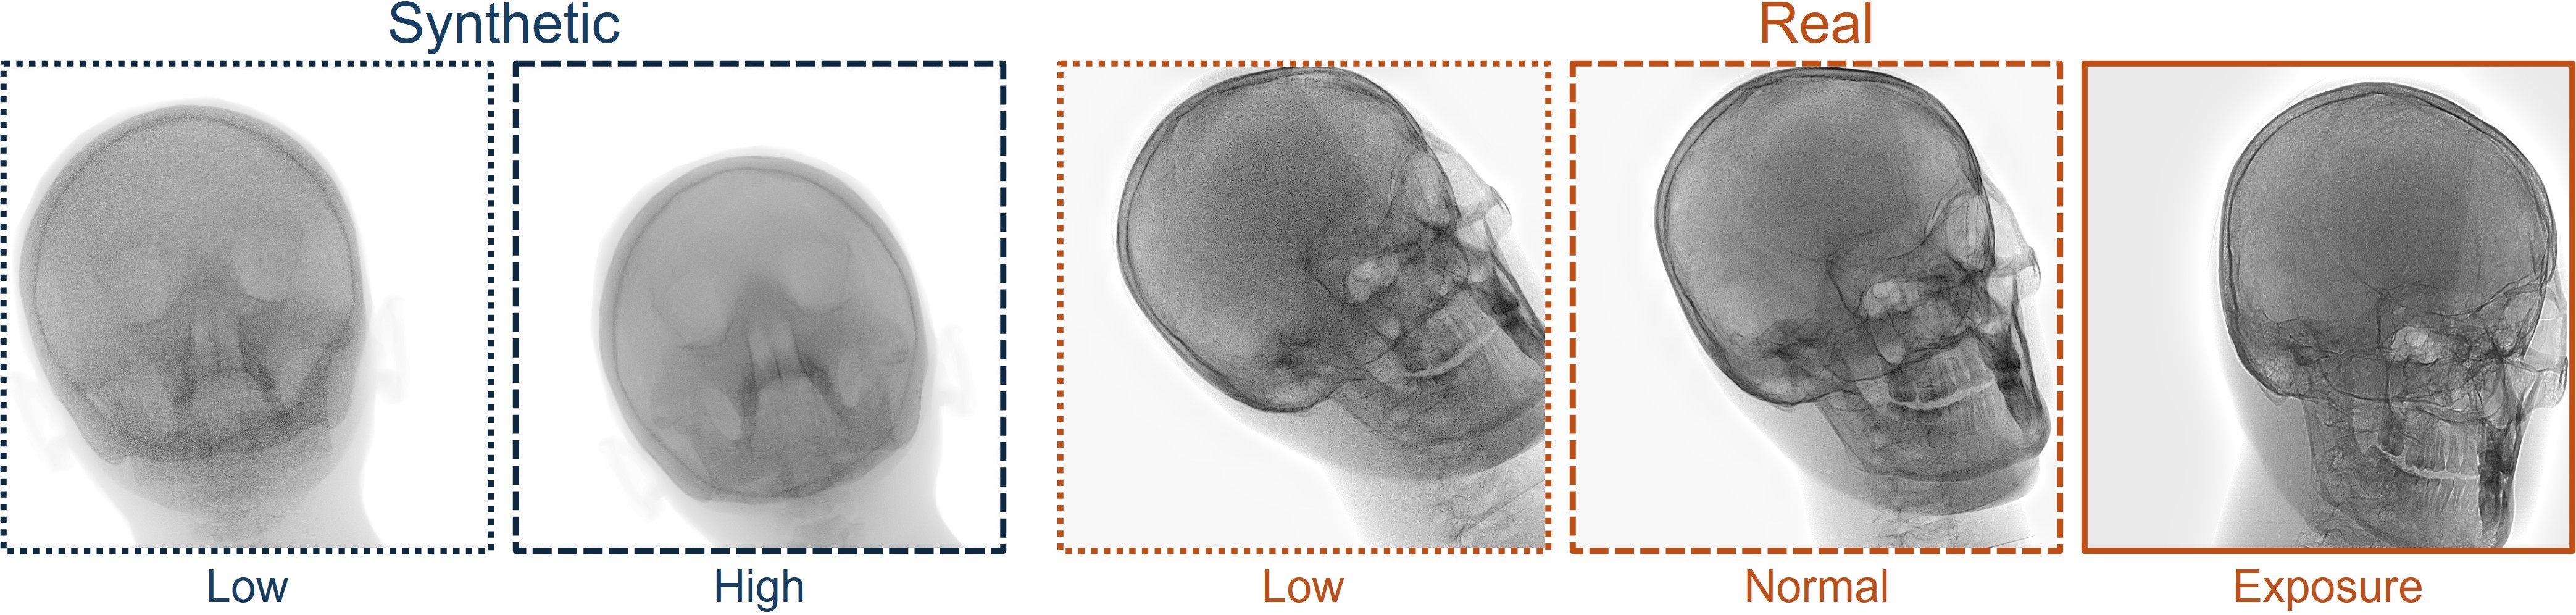

Refer to caption

Figure 2: Dataset overview. The synthetic domain contains Low and High dosage samples generated using the Mentice VIST® simulator; the real domain includes Low, Normal, and Exposure dosage categories acquired from a skull phantom using the Philips Azurion IGT system.

We develop and release a new dataset of real and synthetic head X-ray images, X-DigiSkull, to study the domain adaptation. The dataset consists of synthetic X-ray images of a human skull generated using the Mentice VIST® simulator 111https://www.mentice.com/simulator/vist-g7. Real‑time X‑rays are generated by holding the 3D voxel “patient” head model with per‑voxel attenuation, casting one ray per detector pixel to form a digitally reconstructed radiograph and then approximating scatter, focal‑spot and detector blur, grid/heel effects and detector response, adding quantum/read noise and final image post-processing as the C‑arm and devices move. Real images are acquired from a clinical-grade physical skull phantom using the Philips Azurion Image Guided Therapy (IGT) system. Images are captured from common IGT working positions for neuro procedures. The dataset consists of multiple orientations and is available in three different radiation dose settings: low, normal, and exposure (Philips exclusive), the latter offering enhanced image quality and detail, as shown in Figure 2. This consists of viewing angles rz[40,+40]r_{z}\in[-40^{\circ},+40^{\circ}], ry[40,+40]r_{y}\in[-40^{\circ},+40^{\circ}], rx[40,+40]r_{x}\in[-40^{\circ},+40^{\circ}] with respect to the starting position in 10 increments and up to 3 images at each position to capture the noise present. This results in a total of 2,187 real images. The coordinate systems of the real and synthetic environment are aligned and synthetic images are rendered to approximate the same viewpoints as the real phantom images with the patient table starting at a similar position.The head 3D model used in the simulation is meticulously built from a real clinical case. We capture the synthetic images in finer increments of 5 across the three angles, producing the 5,832 (18318^{3}) images 222Data available at https://zenodo.org/records/16535437. The aim of this alignment is not to achieve precise supervised image translation, but rather to establish a consistent reference structure that preserves spatial features. The composition of the dataset is summarized in Table 1, which contains information on the splits and the number of images available. All images are cropped and resized to 780×\times780 pixels. The test set is obtained by uniformly sampling 15% of viewing angles and corresponding images to ensure a representative distribution. For our experiments, we focus on the task of converting synthetic images at high dose to real images at normal dose.